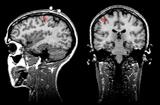

Нужно отметить, что этап наложения электродов остается наиболее трудоемким при проведении ЭЭГ – исследований, он практически не поддается автоматизации и требует участия опытного квалифицированного специалиста. Перспективным направлением решения этих проблемм является метод магнитоэнцефалографии (МЭГ). В нем используются магнитные, а не электрические поля (как при ЭЭГ). МЭГ определяет направление аномальной электрической активности мозга, а не только усиливает сигналы. Многие ученые считают, что МЭГ дополняет ЭЭГ, но его применение в основном пока ограничивается исследовательскими целями [7] (рис.15).

Рис. 15. a) Нейромагнитоэнцефалограф и б) -г) Современные способы представления результатов исследований с помощью ЭВМ (с сайтов http://ntl-cbm.narod.ru/MEG-SITE/index-meg.htm и http://jenameg10.meg.uni-jena.de/gallery.htm)